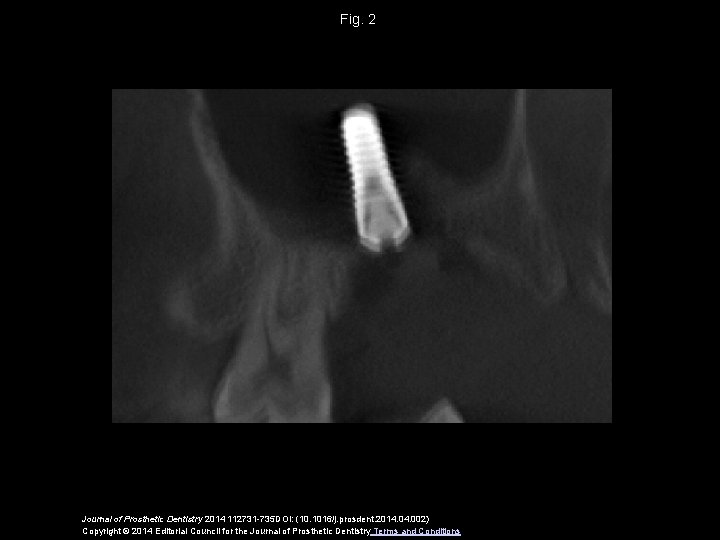

Fig. 2 Journal of Prosthetic Dentistry 2014 112731 -735 DOI: (10. 1016/j. prosdent. 2014. 002) Copyright © 2014 Editorial Council for the Journal of Prosthetic Dentistry Terms and Conditions